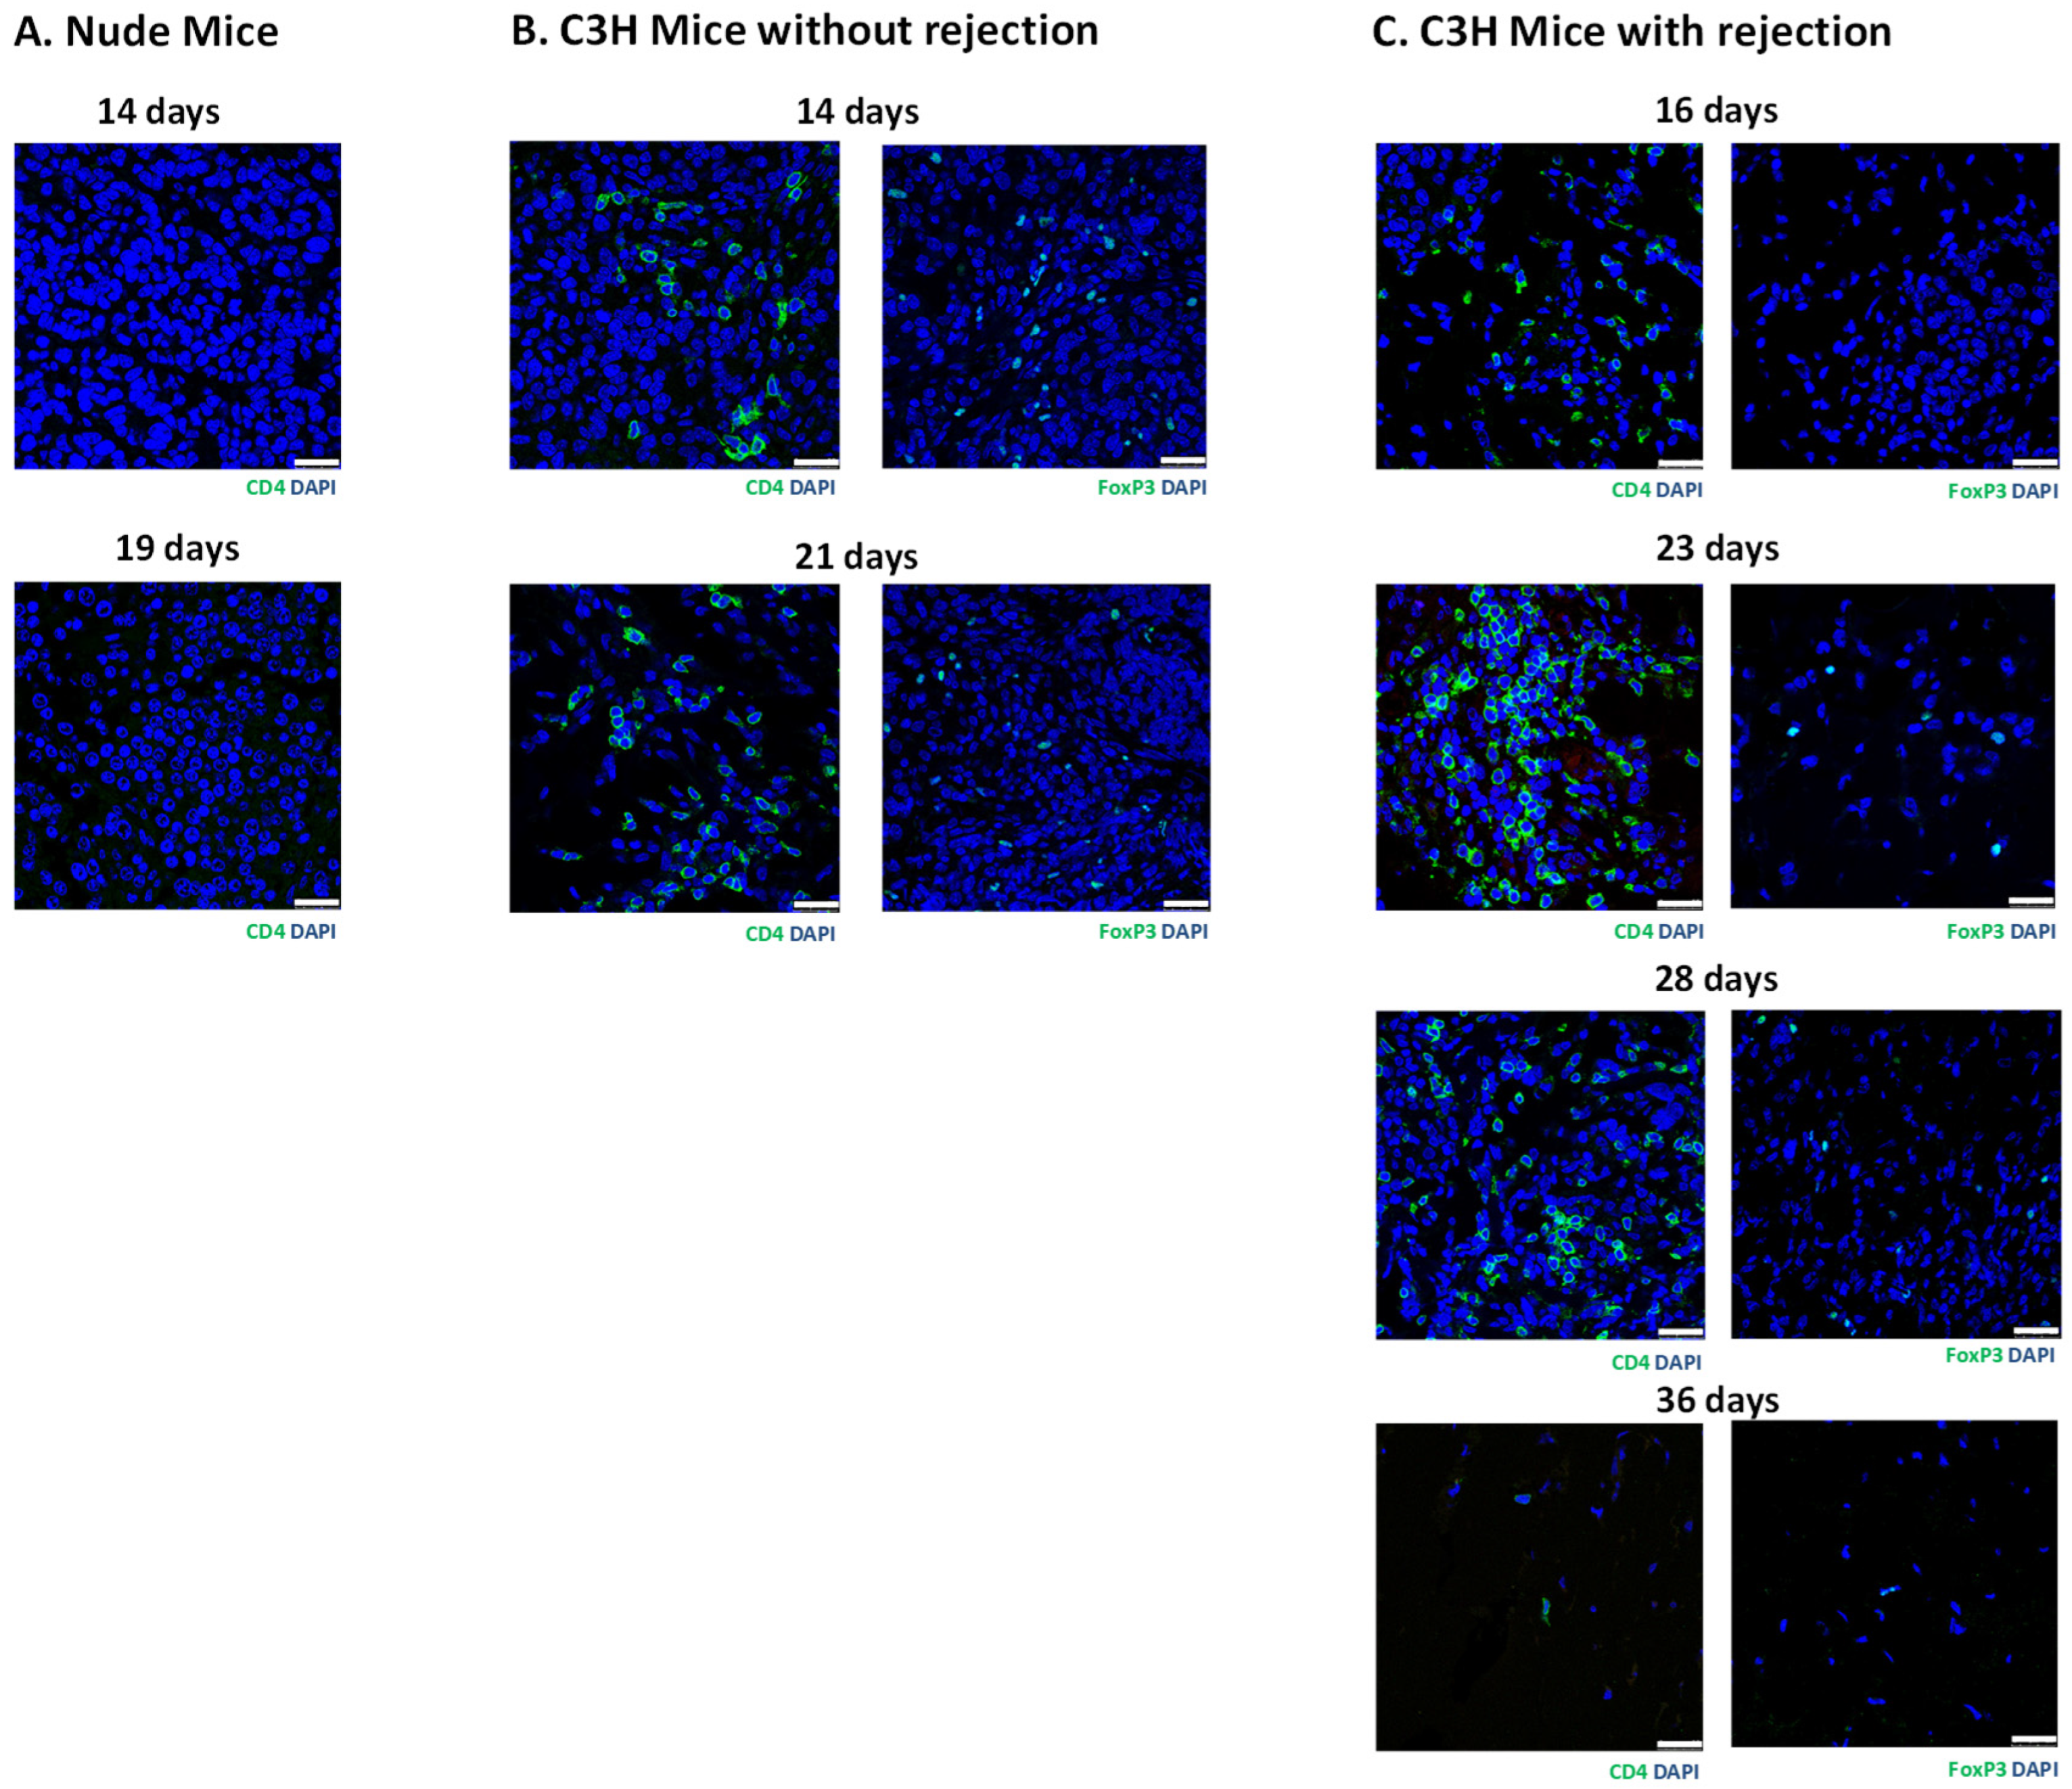

3.3. Histology of Subcutaneous Matrigel-Embedded MIN6 Cell Grafts in Nude and C3H Mice